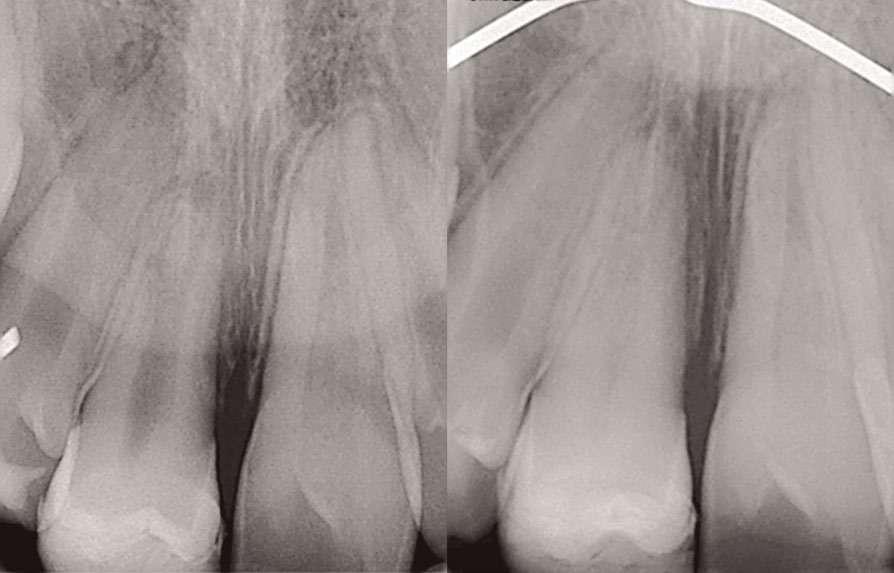

A la exploración intraoral se observaba abombamiento de la cortical lingual en la zona derecha de la mandíbula (Fig. 1). Se realizó un CBCT donde se pudo observar que el diente supernumerario tenía aspecto de premolar, estando alojado de manera

cabalgada entre lingual y vestibular (la corona del diente se encontraba por la zona linguodistal del 44, mientras su raíz se localizaba a nivel interradicular, en íntimo contacto con el nervio dentario inferior.

Dada la cercanía a las raíces de los dientes adyacentes y el riesgo de rizólisis de las mismas, se optó por realizar la exodoncia, utilizando para ello anestesia local de la zona (Fig. 2).

Tal y como se puede observar en las imágenes (Fig. 3 y 4) se realizó una incisión sulcular siguiendo el surco gingivodentario lingual sin descargas para despegar un colgajo a espesor total que facilitó un campo quirúrgico suficiente como para poder realizar la ostectomía hasta descubrir la corona del diente (Fig. 5).

La ostectomía se realizó de manera cuidadosa, tanto con el colgajo y las estructuras del suelo de boca, como con los dientes adyacentes y sus raíces. En este caso el diente no requirió odontosección, por lo que su exodoncia pudo ser completada usando un botador recto y unas pinzas adson para su retirada del alveolo (Fig. 6).

Figuras 1 y 2. Situación inicial y anestesia. Figuras 3 y 4. Incisión y despegamiento del colgajo lingual festoneado.

1 2

Figuras 5 y 6. Ostectomía y exodoncia con botador tipo elevador recto.